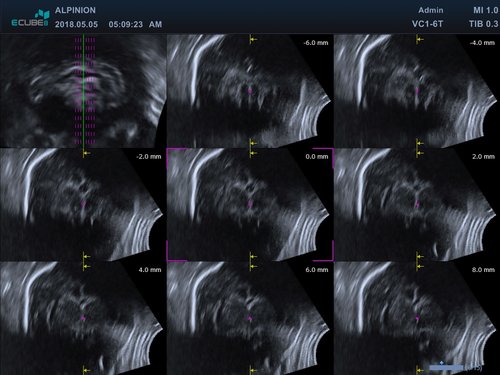

• Konvex: VC1-6T (1-6 MHz) für Ultraschalluntersuchungen in Bereichen Abdomen, Geburtshilfe, Gynäkologie, fetales Echo

• Volume Master, Volume Advance, Live HQ, Auto NT (Geburtshilfe)